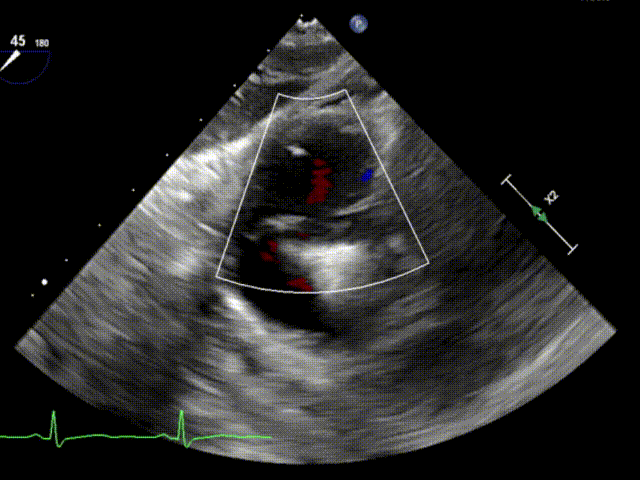

术前TTE+TEE评估

左房增大,右心相对偏大,三尖瓣功能性反流,TypeIIIB(后叶为两瓣),反流程度4+(Massive),反流颈宽约0.52cm,有效反流口面积约0.33cm²,TAPSE为2.11cm,LVEF(%)为61.9%。

第一个夹子释放后(上彩)